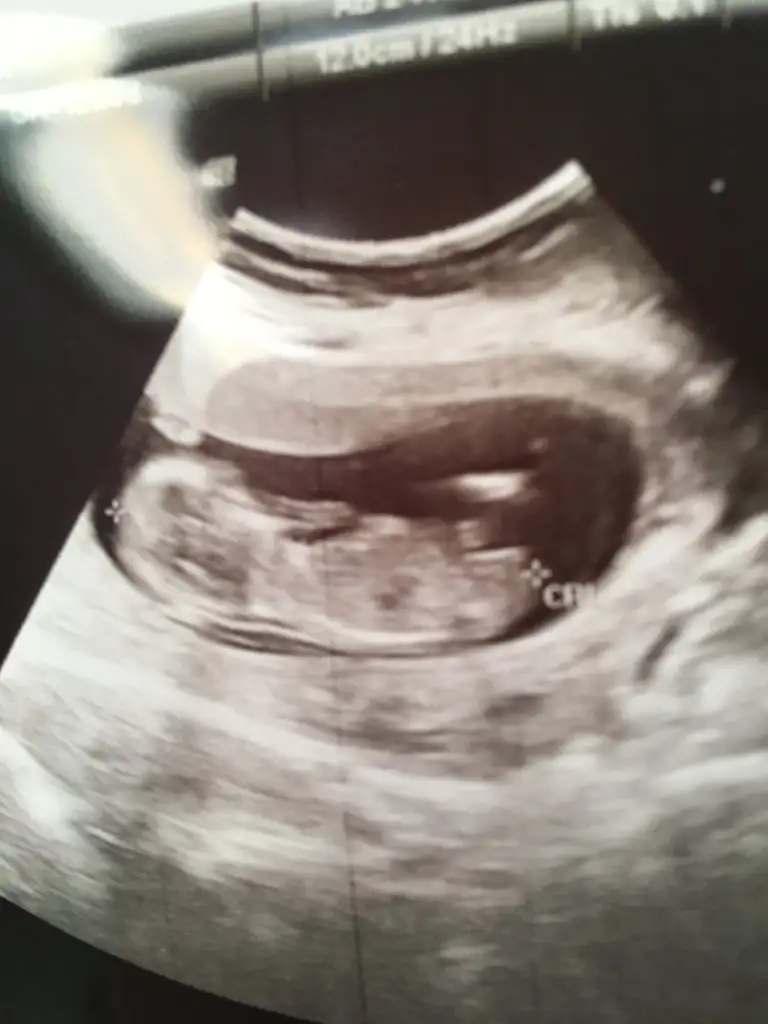

KızEki Görüntüle 2307183 Eki Görüntüle 2307184 kizlar 1. 10 haftalik 2. 12+4 lutfen banada yorum yapin sizce ne

Net degil oyum erkek başka varsa usg paylaşınEki Görüntüle 2307207

Arkadaşlar bebegimin cinsiyetine bakar mısınız 11+6 haftalık 9. Haftalıkken atmıştım ama net değildi şimdi atmak istedim